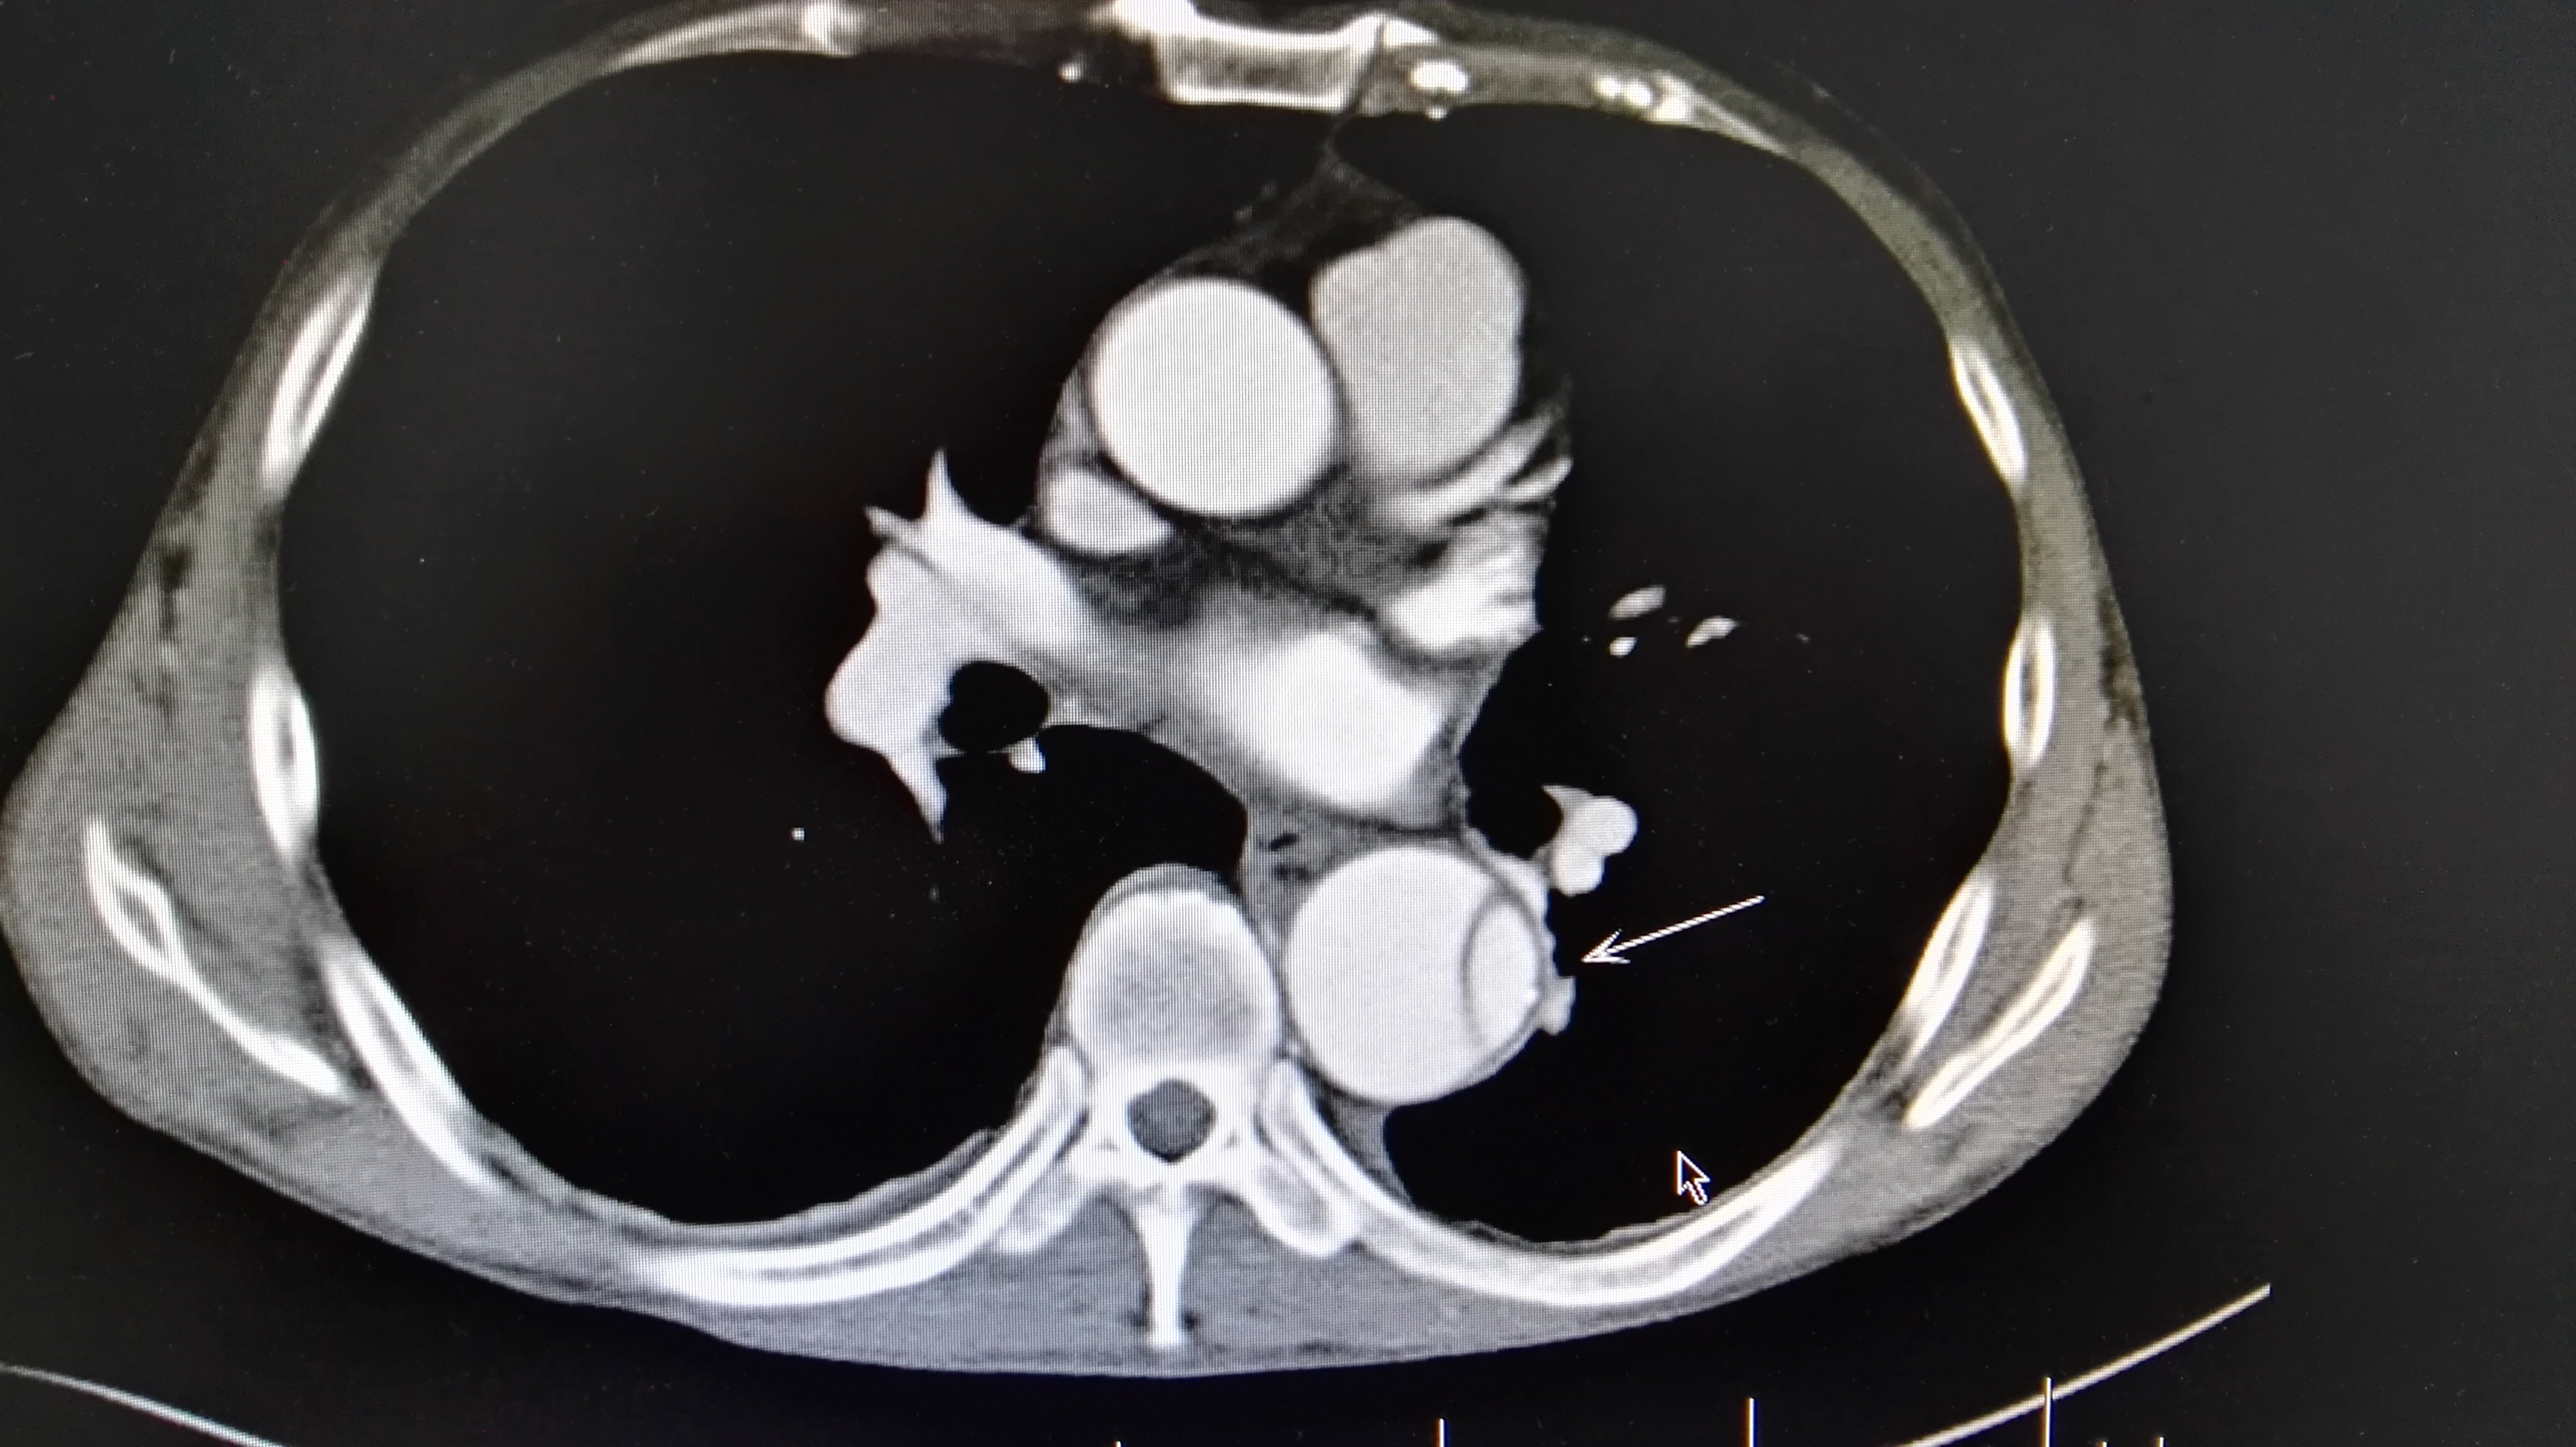

主动脉b型夹层腔内治疗术 - 好大夫在线

图片尺寸4160x2336

诊断主动脉夹层 千万别犯这种错误!

图片尺寸564x433